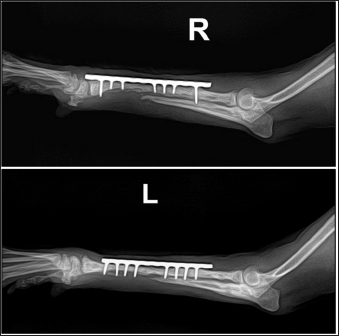

A 3-year and 6-month-old Toy Poodle presented with a history of failed treatment for bilateral radius and ulnar fractures over the course of 1 year. The initial treatment involved plate fixation and linear external fixation; however, repeated implant failure resulted in a non-union fracture (Fig. 1). At the time of presentation, radiographs revealed that most plates, screws, and pins had been removed from both limbs. The prolonged non-union resulted in continued bone resorption at the fracture site without any signs of healing. Loosening was evident around the bone holes where the fixation devices had been applied, and some pins were still visible on the radiographs, indicating they had not been removed. The dog mainly used its hind limbs and exhibited a plantigrade gait when moving the forelimb. Overall systemic conditions were satisfactory. No specific abnormalities were found in the skin surrounding the fracture site or pin insertions, and blood tests showed normal results, except for a slight increase in alkaline phosphatase. The diagnosis was confirmed as non-union fractures of the radius and ulna in both forelimbs.

Fig. 1. Bilateral radiographs of the radius and ulna, showing osteolytic bone holes at previous screw sites and nonunion at the fracture sites.